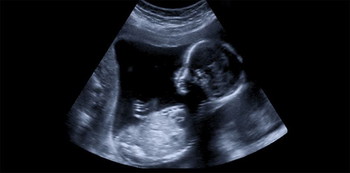

Kajian menggunakan imbasan ultrasound untuk mengenalpasti pergerakan muka fetus. Si kecil ini sebenarnya menunjukkan menurunkan kening dan mengerut hidung. Kajian ini juga mengkaji video imbasan 4D oleh 8 perempuan dan 7 bayi lelaki di dalam rahim.